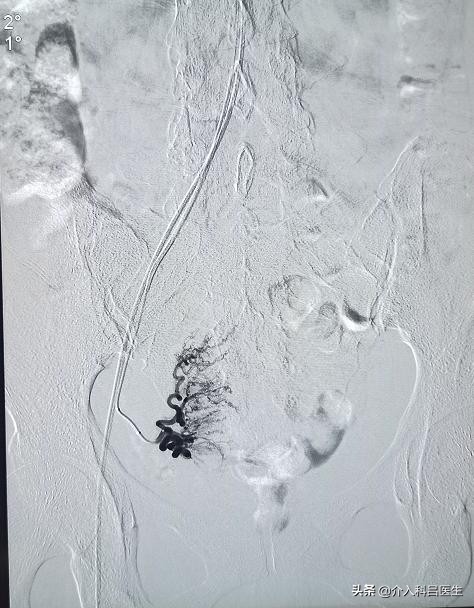

介入治疗一招解决子宫肌瘤

得了子宫肌瘤,很多患者采取子宫肌瘤剔除手术或者直接切除子宫,可是大家都知道,剔除手术的复发率是比较高的,尤其是对多发性的肌瘤,为什么?很多子宫肌瘤患者长了两个三个肌瘤,甚至十多个,并且肌瘤大小不一,有的可能大的和小的融合到一起了。

开刀或者腹腔镜手术剔除肌瘤,有时候它不能把所有肌瘤都剔除干净,大的可能剔除了,有些只有几毫米的小的,可能就没有剔除干净。

这样,因为子宫内的环境没有改变,小的肌瘤得到了更多养分,就会长大,这就又复发了。

介入治疗从根源切断病灶,不用切除子宫,也不影响有生育要求的女性再怀孕!